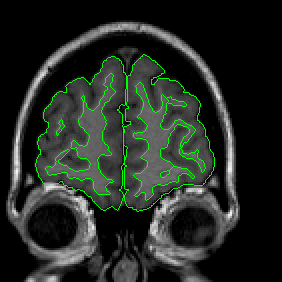

The insular cortex is “hidden” between the temporal and inferior parietal corticies. By drawing sulci lines in the sagittal view, we gain an outline of it in the coronal. Choose a sagittal slice where insula is clearly visible (Fig 1), then draw a “circle” around it (Fig 2). Do this for several slices and for both hemispheres.

Figure 1              Figure

2

Once you have drawn your sulci lines, the insula should be clearly outlined (by little dots) in the coronal view (Fig 3). This is particularly useful in the more anterior slices.

Figure 3